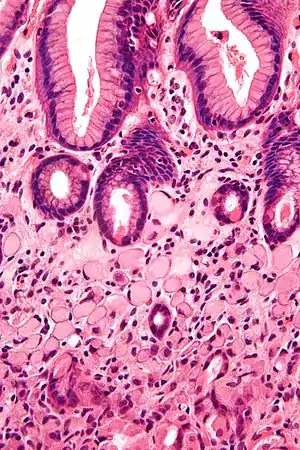

| A signet ring cell carcinoma of the stomach. Signet ring cells are seen in the lower half of the image. Gastric epithelium is seen in the upper half of the image. H&E stain. | |

SRCCs are named due to their resemblance to signet rings, which result from the formation of large vacuoles full of mucin that displace the nucleus to the cell's periphery.[15]